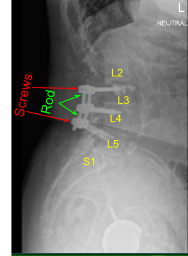

Este paciente había sido sometido previamente a una artrodesis instrumentada en una instalación externa en L3-5. Presentaron dolor en la parte anterior derecha del muslo y en la pierna posterior izquierda. Las imágenes mostraron una degeneración del segmento adyacente por encima y por debajo de su masa de fusión que se correlacionaba bien con sus síntomas.

En esta etapa, la atención se dirigió a la incisión de la línea media caudal que se abrió bruscamente y se desmontó con electrocauterio monopolar y elevadores de Cobb. Esta incisión, aunque tomada sobre la cicatriz anterior de la línea media, se centró sobre la faceta derecha L4-5 y la cabeza derecha del tulipán del tornillo pedicular L5 que se visualizó claramente. El nivel y la posición se confirmaron con fluoroscopia AP.

La lámina y las pars del nivel L5 en el lado derecho quedaron expuestas, al igual que la unión espinolaminar L5 y la unión facetaria de la lámina. De la misma manera que arriba, se realizó una laminoforaminotomía L5 del lado derecho con un taladro midas rex de alta velocidad y una combinación de curetas y Kerrison rongeurs. Esto se llevó a cabo en la medida en que la raíz transversal de S1 derecha se vio y se descomprimió en los agujeros proximales. El foramen L5 derecho también se descomprimió.